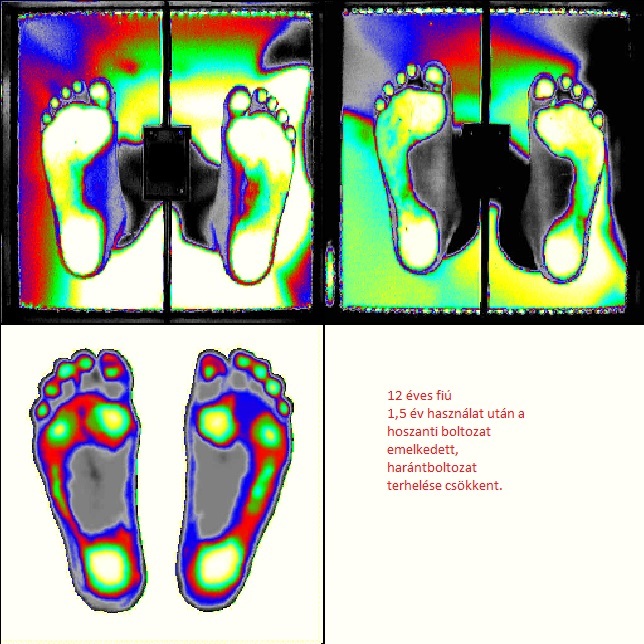

Az egyedi talpbetét rendelést, egy számítógépes talpvizsgálat előzi meg, mely során feltárjuk a láb statikai elváltozásait. Az eljárás teljesen fájdalommentes és nagyjából 5-10 percet vesz igénybe.